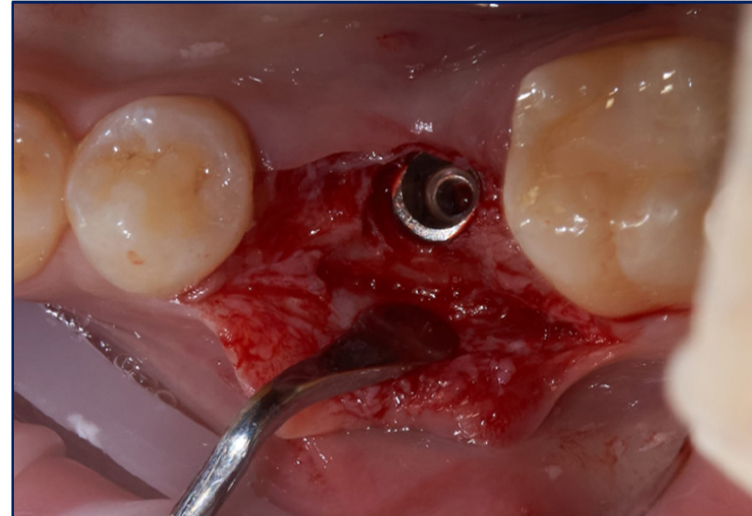

В ходе операции был реализован комбинированный лоскут, с расщепленной частью в апроксимальных и апикальных участках, с целью создания оптимальных условий для кератинизации, реваскуляризации и созревания используемого соединительно-тканного трансплантата. Платформа дентального имплантата (Osstem 4,5/10) спозиционирована субкрестально на 3 мм с целью компенсации вертикального дефицита мягких тканей для формирования биологической ширины (рис. 2).